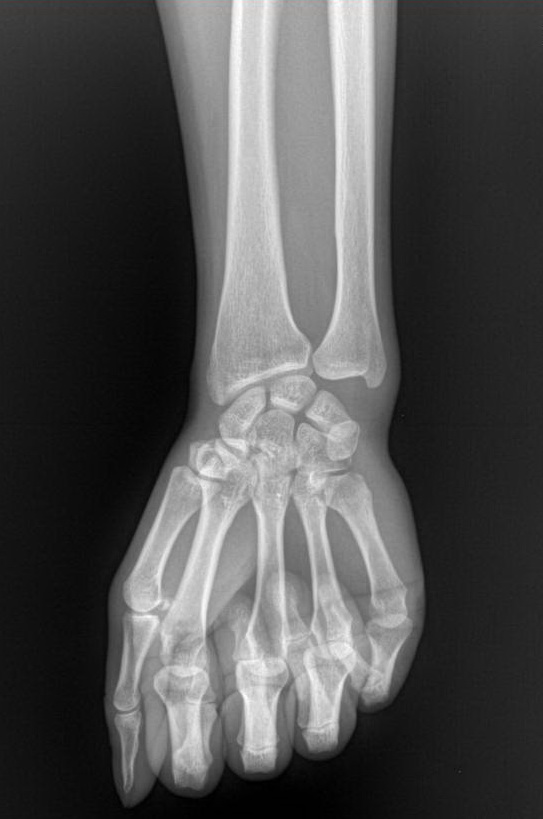

标题: X7319:F 50岁,左腕肿痛数年 [打印本页]

标题: X7319:F 50岁,左腕肿痛数年

大多角骨无菌性坏死可能。

大多角骨密度增高,尺骨过长,应该考虑到尺骨撞击综合征

大多角骨密度增高,尺骨过长,应该考虑到尺骨撞击综合征,完善病史。

我怎么看都感觉多角骨有问题,怎么大家都认为“未见异常”呢?难道是《皇帝的新衣》吗?哈哈哈哈哈!

考虑多角骨无菌性坏死可能。具体是大还是小多角骨,判断不了。